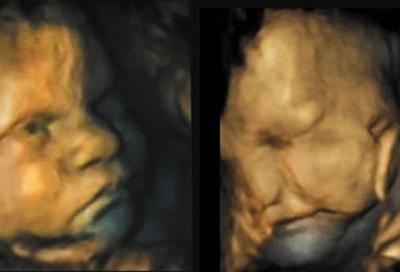

研究指婴儿在出生前16周已会做表情

研究指婴儿在出生前16周已会做表情 (蜘蛛网)据香港媒体报道,英国达勒姆大学的...